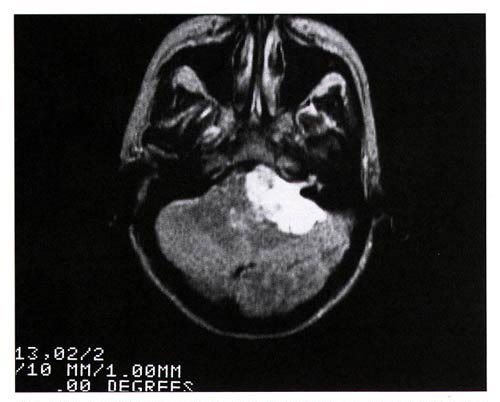

Figure 14 is an axial (cross-sectional) image of the brain showing a tumor of the cerebellum (white areas) in the midline. Figure 14c is a magnified image showing the picture elements or "pixels" (small squares) that make up the image. The cerebellar tumor as it would appear (D) with no MR signal differences. Figure D is the same image as B but where all MR signal differences were eliminated and all the MR pixels therefore had the same pixel brightness. The absence of the MR signal differences between cancer and normal tissue discovered by Damadian gives the MR image pixels equal brightness and the tumor becomes Invisible. |

Were the amplitudes of the NMR signals (fig.9) used to set the brightness of each MRI image pixel the same for all tissues (and prior to Dr. Damadian's discovery such NMR tissue signal differences were not known to exist) the brightness of each image pixel would be the same. The MR image would be a blank.

These signal amplitude differences enabled cancer tissues (Figures 11-13) and other tissues to be visualized in MRI images because the signal differences generate the needed brightness differences "PIXEL CONTRAST (IMAGE DETAIL)" in the picture elements (pixels) needed to visualize detail in the MRI image. The CONTRAST

in pixel brightness, "PIXEL

CONTRAST (IMAGE DETAIL)", allows the cancer

pixels in the image to be distinguished from the surrounding

normal pixels. (Figs 11-13) NO SIGNAL

AND THE TUMOR IS

INVISIBLE !! The cerebellar tumor as it would appear (14-D) with no MR signal differences. Figure 14-D is the same image as Figure 14-B but where all MR signal differences were eliminated and all the MR pixels therefore had the same pixel brightness. The absence of the MR signal differences between cancer and normal tissue DISCOVERED BY DAMADIAN gives the MR image pixels equal brightness and NO SIGNAL DIFFERENCES:

THE IMAGE IS A BLANK THE SIGNAL MAKES THE IMAGE !!